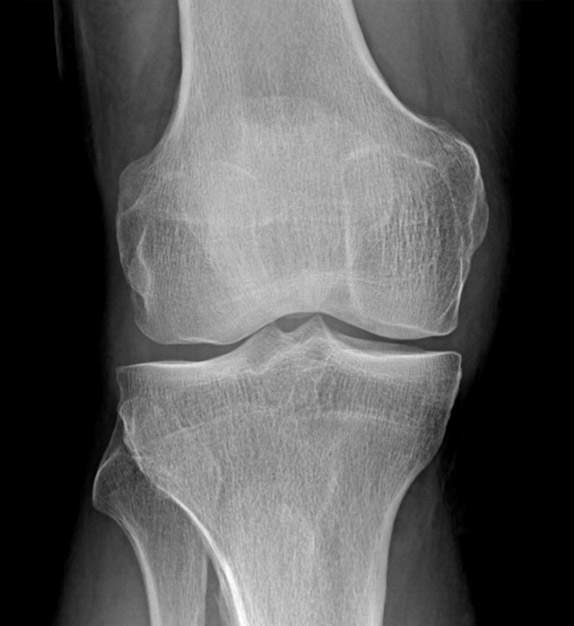

Examinarea prin computer tomograf a genunchiului este indicată în traumatismele cu suspiciune de fractură, dar și în alte patologii atunci când examinarea prin rezonanță magnetică nu este disponibilă sau este contraindicată.

Examinarea prin computer tomograf durează câteva zeci de secunde, în funcție de rapiditatea computer tomografului. Poziția pacientului este similară cu cea de la rezonanță magnetică.

Achiziția imaginilor se face după protocoale dedicate articulațiilor mari, în care avem nevoie de o scanare fină. Scanarea trebuie să se limiteze la zona de interes pentru a nu iradia inutil pacientul, dar fără să scăpăm din vedere faptul că fracturile, mai ales cele spiroide, pot fi foarte lungi și trebuie să avem în imagine tot traiectul.